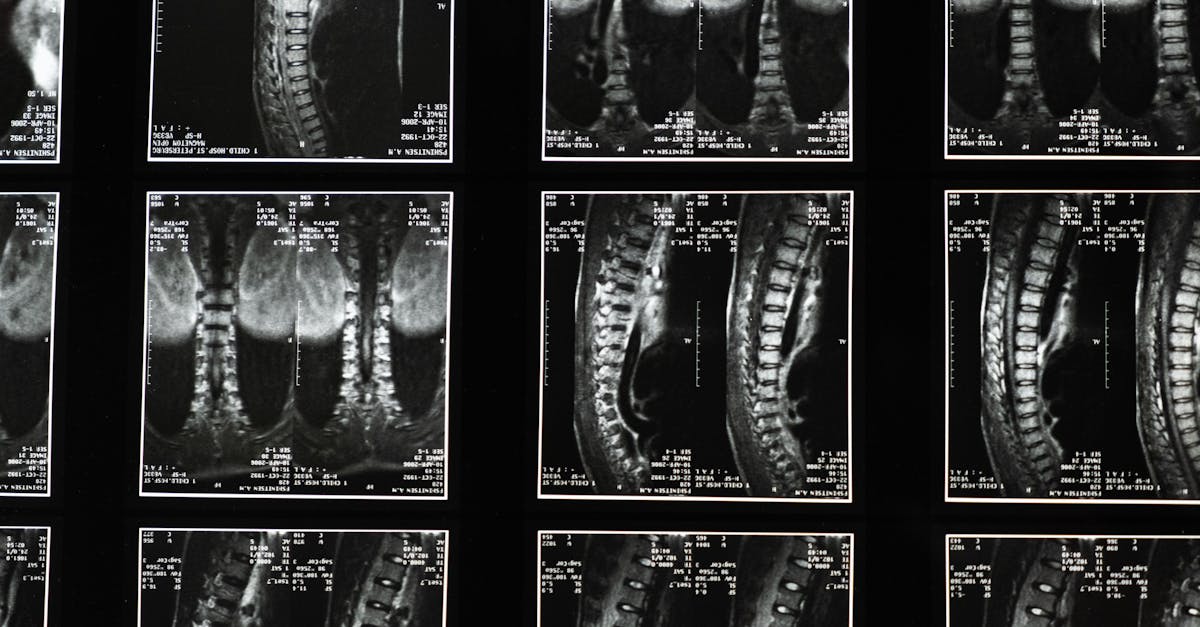

Les douleurs nocturnes peuvent être particulièrement handicapantes. Elles empêchent un sommeil réparateur, provoquant fatigue et irritabilité. Plusieurs facteurs contribuent à ces douleurs, notamment les tensions nerveuses causées par des déséquilibres dans la colonne vertébrale. Les pathologies comme les hernies discales peuvent être à l’origine de cette douleur, en comprimant les nerfs et en provoquant une gêne accrue la nuit.

La décompression neurovertébrale applique une traction douce sur la colonne vertébrale. Cette méthode augmente l’espace entre les vertèbres, réduisant ainsi la pression sur les disques intervertébraux. Cela permet aux disques de se réhydrater et de récupérer, améliorant leur capacité à absorber les chocs. En libérant la pression sur les nerfs, il est possible de diminuer l’inflammation et de favoriser un meilleur flux sanguin vers la région, contribuant au soulagement des douleurs.

La décompression neurovertébrale repose sur l’application d’une traction douce et contrôlée sur la colonne vertébrale. Lorsque ce traitement est effectué, un espace est créé entre les vertèbres, ce qui réduit la pression exercée sur les disques intervertébraux et les nerfs environnants. Ce processus favorise la réhydratation des disques, permettant une meilleure absorption des chocs et une circulation sanguine améliorée. En relâchant les tensions sur les nerfs, la décompression neurovertébrale aide à réduire les symptômes douloureux souvent exacerbés durant la nuit.

Réduction de la compression nerveuse

Les douleurs nocturnes complexes sont souvent liées à des cas de compression nerveuse, entraînant des sensations désagréables et des inconforts lors du coucher. La décompression neurovertébrale cible spécifiquement ces zones de compression en agissant sur les disques intervertébraux, permettant ainsi une meilleure circulation sanguine et une diminution des inflammations. Cela conduit à un soulagement des douleurs aiguës qui perturbent le sommeil des patients, leur permettant de mieux se reposer la nuit.

Les douleurs nocturnes sont fréquemment liées à des problèmes sous-jacents tels que les hernies discales, la sténose spinale ou d’autres conditions qui provoquent une compression des nerfs. Ces douleurs peuvent perturber le sommeil, affectant ainsi la qualité de vie des patients qui peinent à trouver une position confortable pour dormir. La décompression neurovertébrale, en relâchant la pression sur ces nerfs, aide à atténuer les sensations de douleur et d’inconfort qui émergent souvent lors de la nuit.

Les mécanismes d’action de la décompression neurovertébrale sont multiples. Lors de la séance, un appareil spécifique applique une traction douce sur la colonne vertébrale, ce qui crée une pression négative à l’intérieur des disques intervertébraux. Ce phénomène aide à attirer des nutriments et des fluides dans les disques, favorisant ainsi leur régénération et leur réhydratation. De plus, cette technique réduit l’inflammation autour des nerfs, ce qui est essentiel pour soulager les douleurs chroniques.